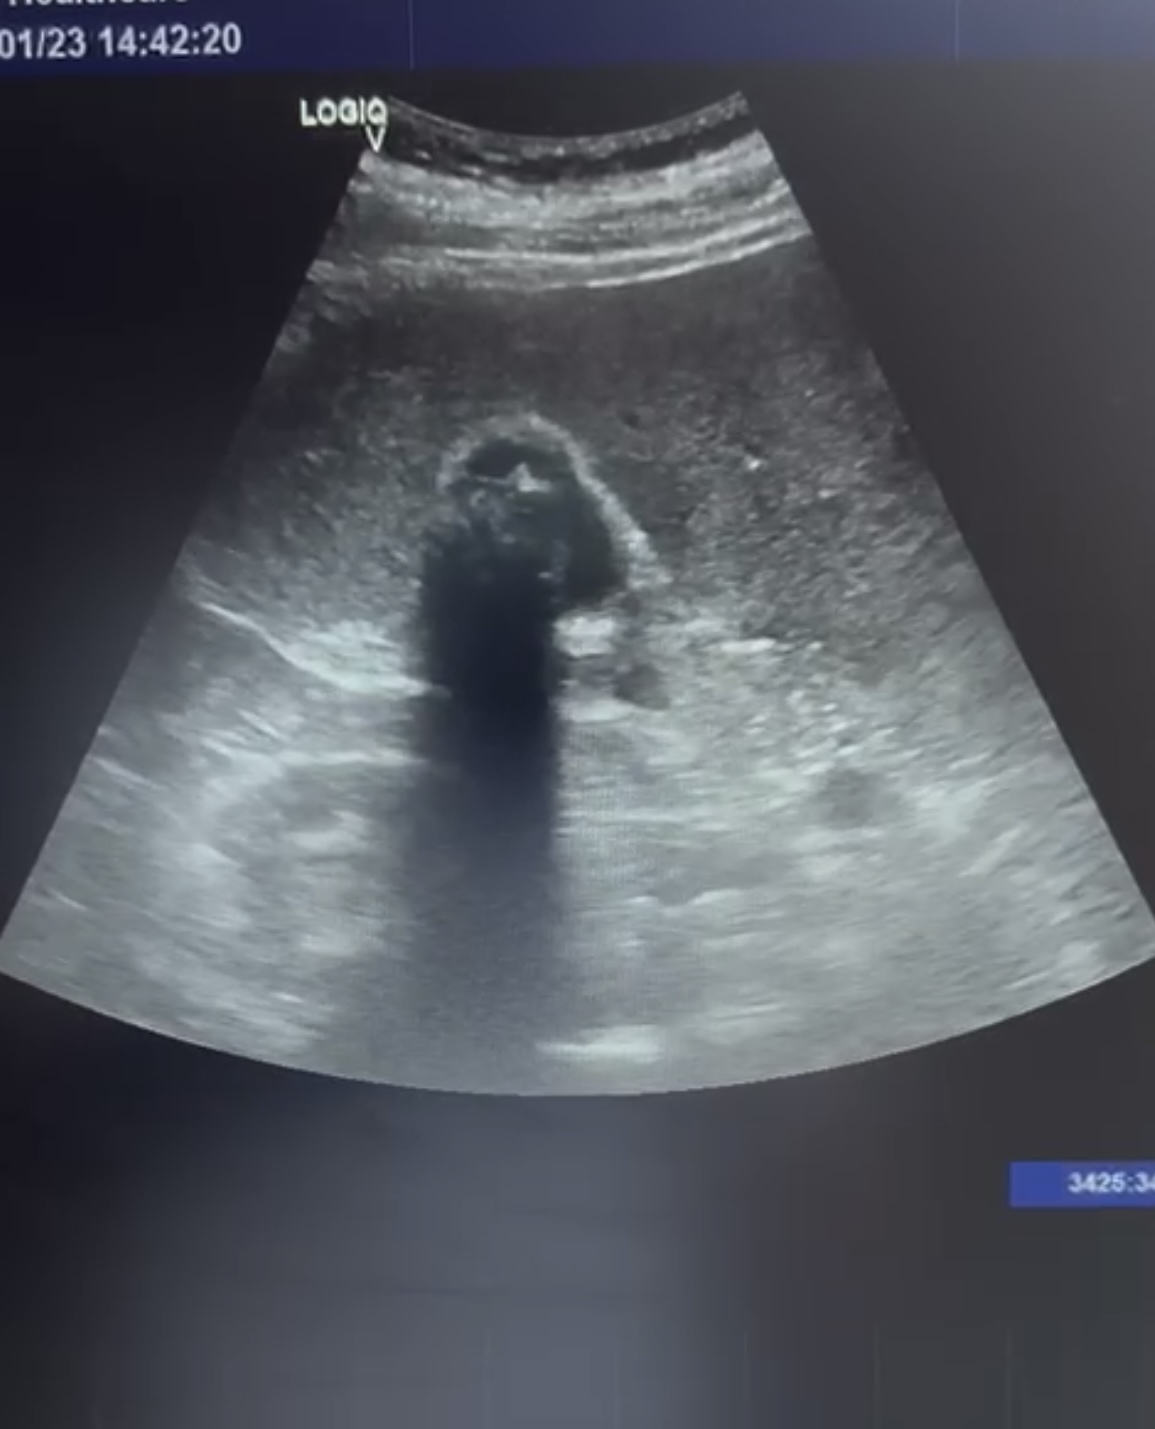

Se observa la vesícula biliar con varias litiasis en su interior y sombra acústica posterior. No se observan signos de colecistitis ni dilatacion de la vía biliar.